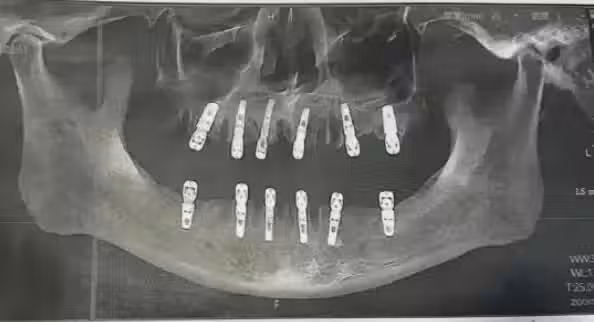

黃先生結束植牙手術後,一直感覺牙齒疼痛不止,在術後13天因心臟驟停死亡,噩耗來得措手不及,黃先生的女兒悲痛表示: 「沒想到我爸走得那麼快,給他買的新車都沒來得及開......」更控訴動手術的德維口腔醫院,手術同意書上寫的與工作人員介紹的注意事項不符!

圖/翻攝自 微博